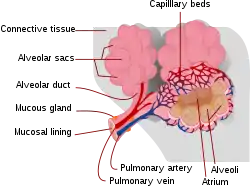

Alveoli are first located in the respiratory bronchioles that mark the beginning of the respiratory zone. They are located sparsely in these bronchioles, line the walls of the alveolar ducts, and are more numerous in the blind-ended alveolar sacs.[5] The acini are the basic units of respiration, with gas exchange taking place in all the alveoli present.[6] The alveolar membrane is the gas exchange surface, surrounded by a network of capillaries. Oxygen is diffused across the membrane into the capillaries and carbon dioxide is released from the capillaries into the alveoli to be breathed out.[7][8]

The alveoli are first located in the respiratory bronchioles as scattered outpockets, extending from their lumens. The respiratory bronchioles run for considerable lengths and become increasingly alveolated with side branches of alveolar ducts that become deeply lined with alveoli. The ducts number between two and eleven from each bronchiole.[10] Each duct opens into five or six alveolar sacs into which clusters of alveoli open.

Each terminal respiratory unit is called an acinus and consists of the respiratory bronchioles, alveolar ducts, alveolar sacs, and alveoli. New alveoli continue to form until the age of eight years.[5]